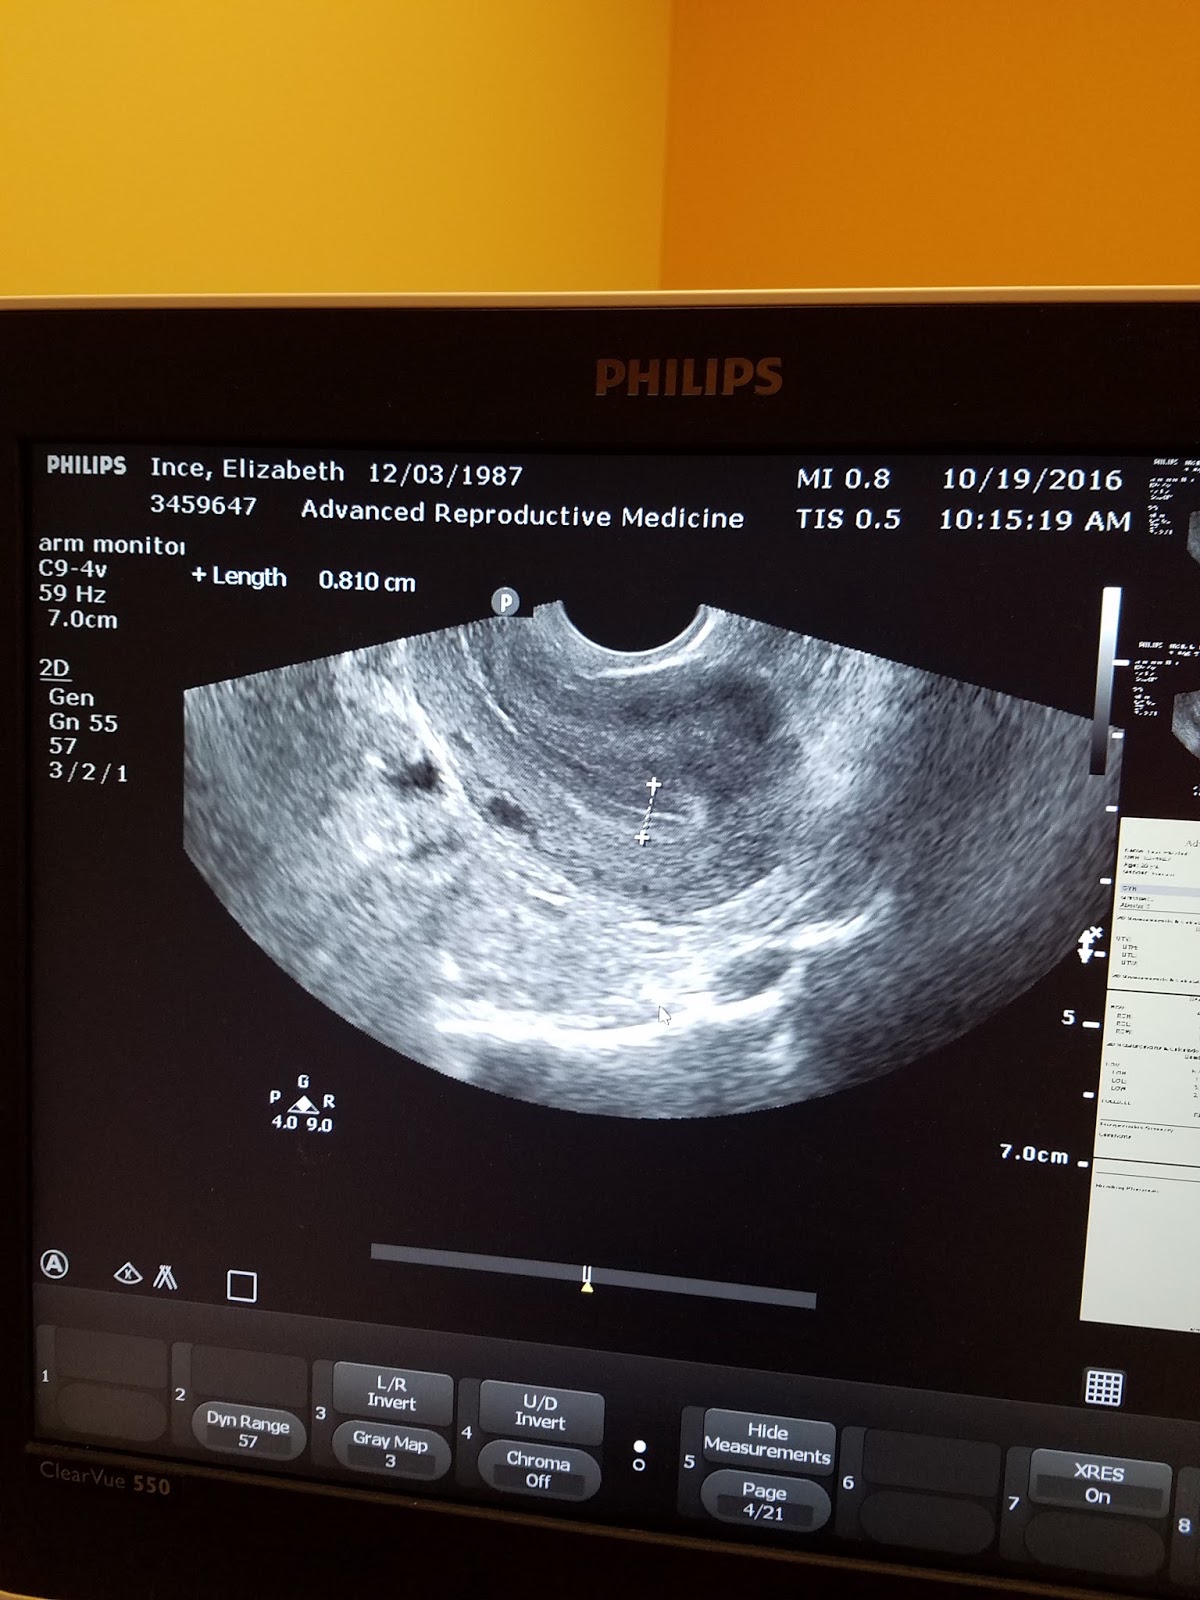

On Wednesday I had another ultrasound to check the lining.  I was told we are at an 8.1. I continued the medication and had another ultrasound yesterday along with blood work.  The ultrasound tech seemed concerned and kept looking back in my chart, naturally making me a little nervous.  Once she finished she said the "Dr would be right in" again raising a red flag since the Dr never came into the room since they just do the monitoring.

One of the Dr's  came in and asked when the transfer was planned, I told her next Thursday. She responded "good! If you were my patient I would be very happy with this uterus." She continued to say that the shape and structure were perfect. "Triple striped " and the thickness was perfect at 11.8.

Monday I had the repeat ultrasound for my baseline lining. As soon as the image appeared on the screen the nurse said "I'm sure they will be very happy with this" my lining was at 3.8. Later that afternoon I got a call saying I could start meds. That day I got a new calendar showing the medication schedule with a planned transfer on Oct 27th if all goes well

So yesterday 10/7 I had an ultrasound to check my lining so I could start the meds. Well my lining was to thick at 7.1. So the Fertility Dr office called and said I couldn't start meds until my lining was thinner. So now I have to have another ultrasound Monday. In a scramble to find someone to work for me I found someone so I could make the 2+ hour round trip drive for an ultrasound in hopes of a thinner lining.